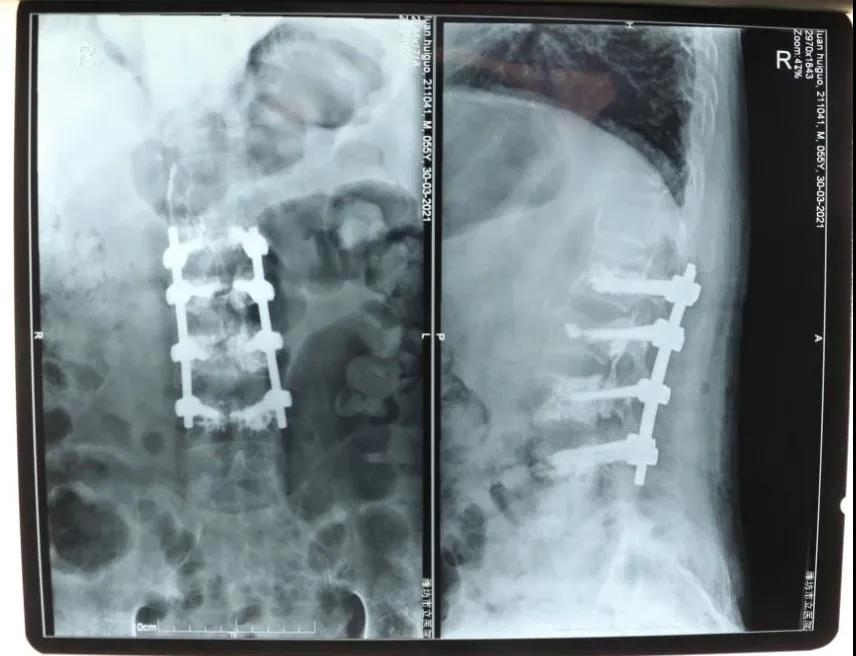

骨一科經(jīng)椎弓根椎體植骨,骨水泥加強(qiáng)釘棒治療

欒先生4天前突然感到腰背部疼痛,活動(dòng)不便,幾天下來(lái)也沒(méi)有明顯好轉(zhuǎn),于是來(lái)到我院就診。經(jīng)拍片檢查發(fā)現(xiàn)欒先生腰椎椎體壓縮性骨折,同時(shí)患者還有重度骨質(zhì)疏松癥。27日,創(chuàng)傷外科主任、骨一科副主任孫守全為患者實(shí)施了椎體壓縮骨折后路切開(kāi)復(fù)位、椎體植骨、骨水泥注入、釘棒撐開(kāi)內(nèi)固定手術(shù),成功為患者解除了病痛的困擾。該手術(shù)是我院首例經(jīng)椎弓根椎體植骨,骨水泥加強(qiáng)釘棒治療手術(shù),標(biāo)志著骨科醫(yī)療技術(shù)發(fā)展逐步成熟、不斷攻克新難關(guān),是廣大患者醫(yī)治病痛的可靠力量。